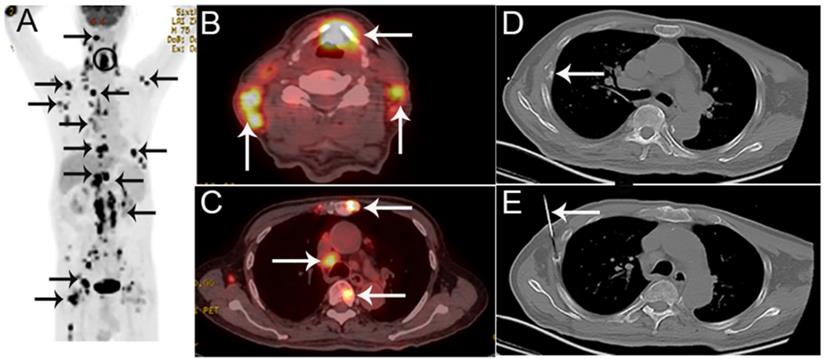

Figure 1

A 44-year-old man presented with back pain, suspected of lung cancer with bone metastasis by PET/CT. A The coronal maximum intensity projection FDG PET image shows multiple FDG-avid lesions in the lung, a mediastinal lymph node and in L1. B,C The axial FDG PET image (B) and fusion images (C) show a FDG-avid lesion (SUVmax 6.7) in L1. D,E The corresponding CT image (D) and the biopsy under CT guidance (E). Histological examination confirmed that the bone lesion was metastatic lung adenocarcinoma. EGFR and ALK were detected as wild and negative, respectively.